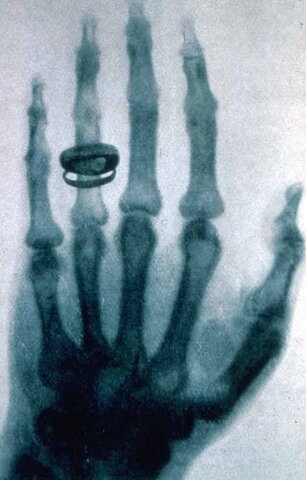

Roentgen produjo y publico la primera imagen de rayos X medica